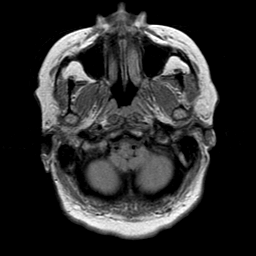

Cerebral hemorrhage, MR Study mr-pd -- Slice #3

[Home][Help][Clinical] Slice 3